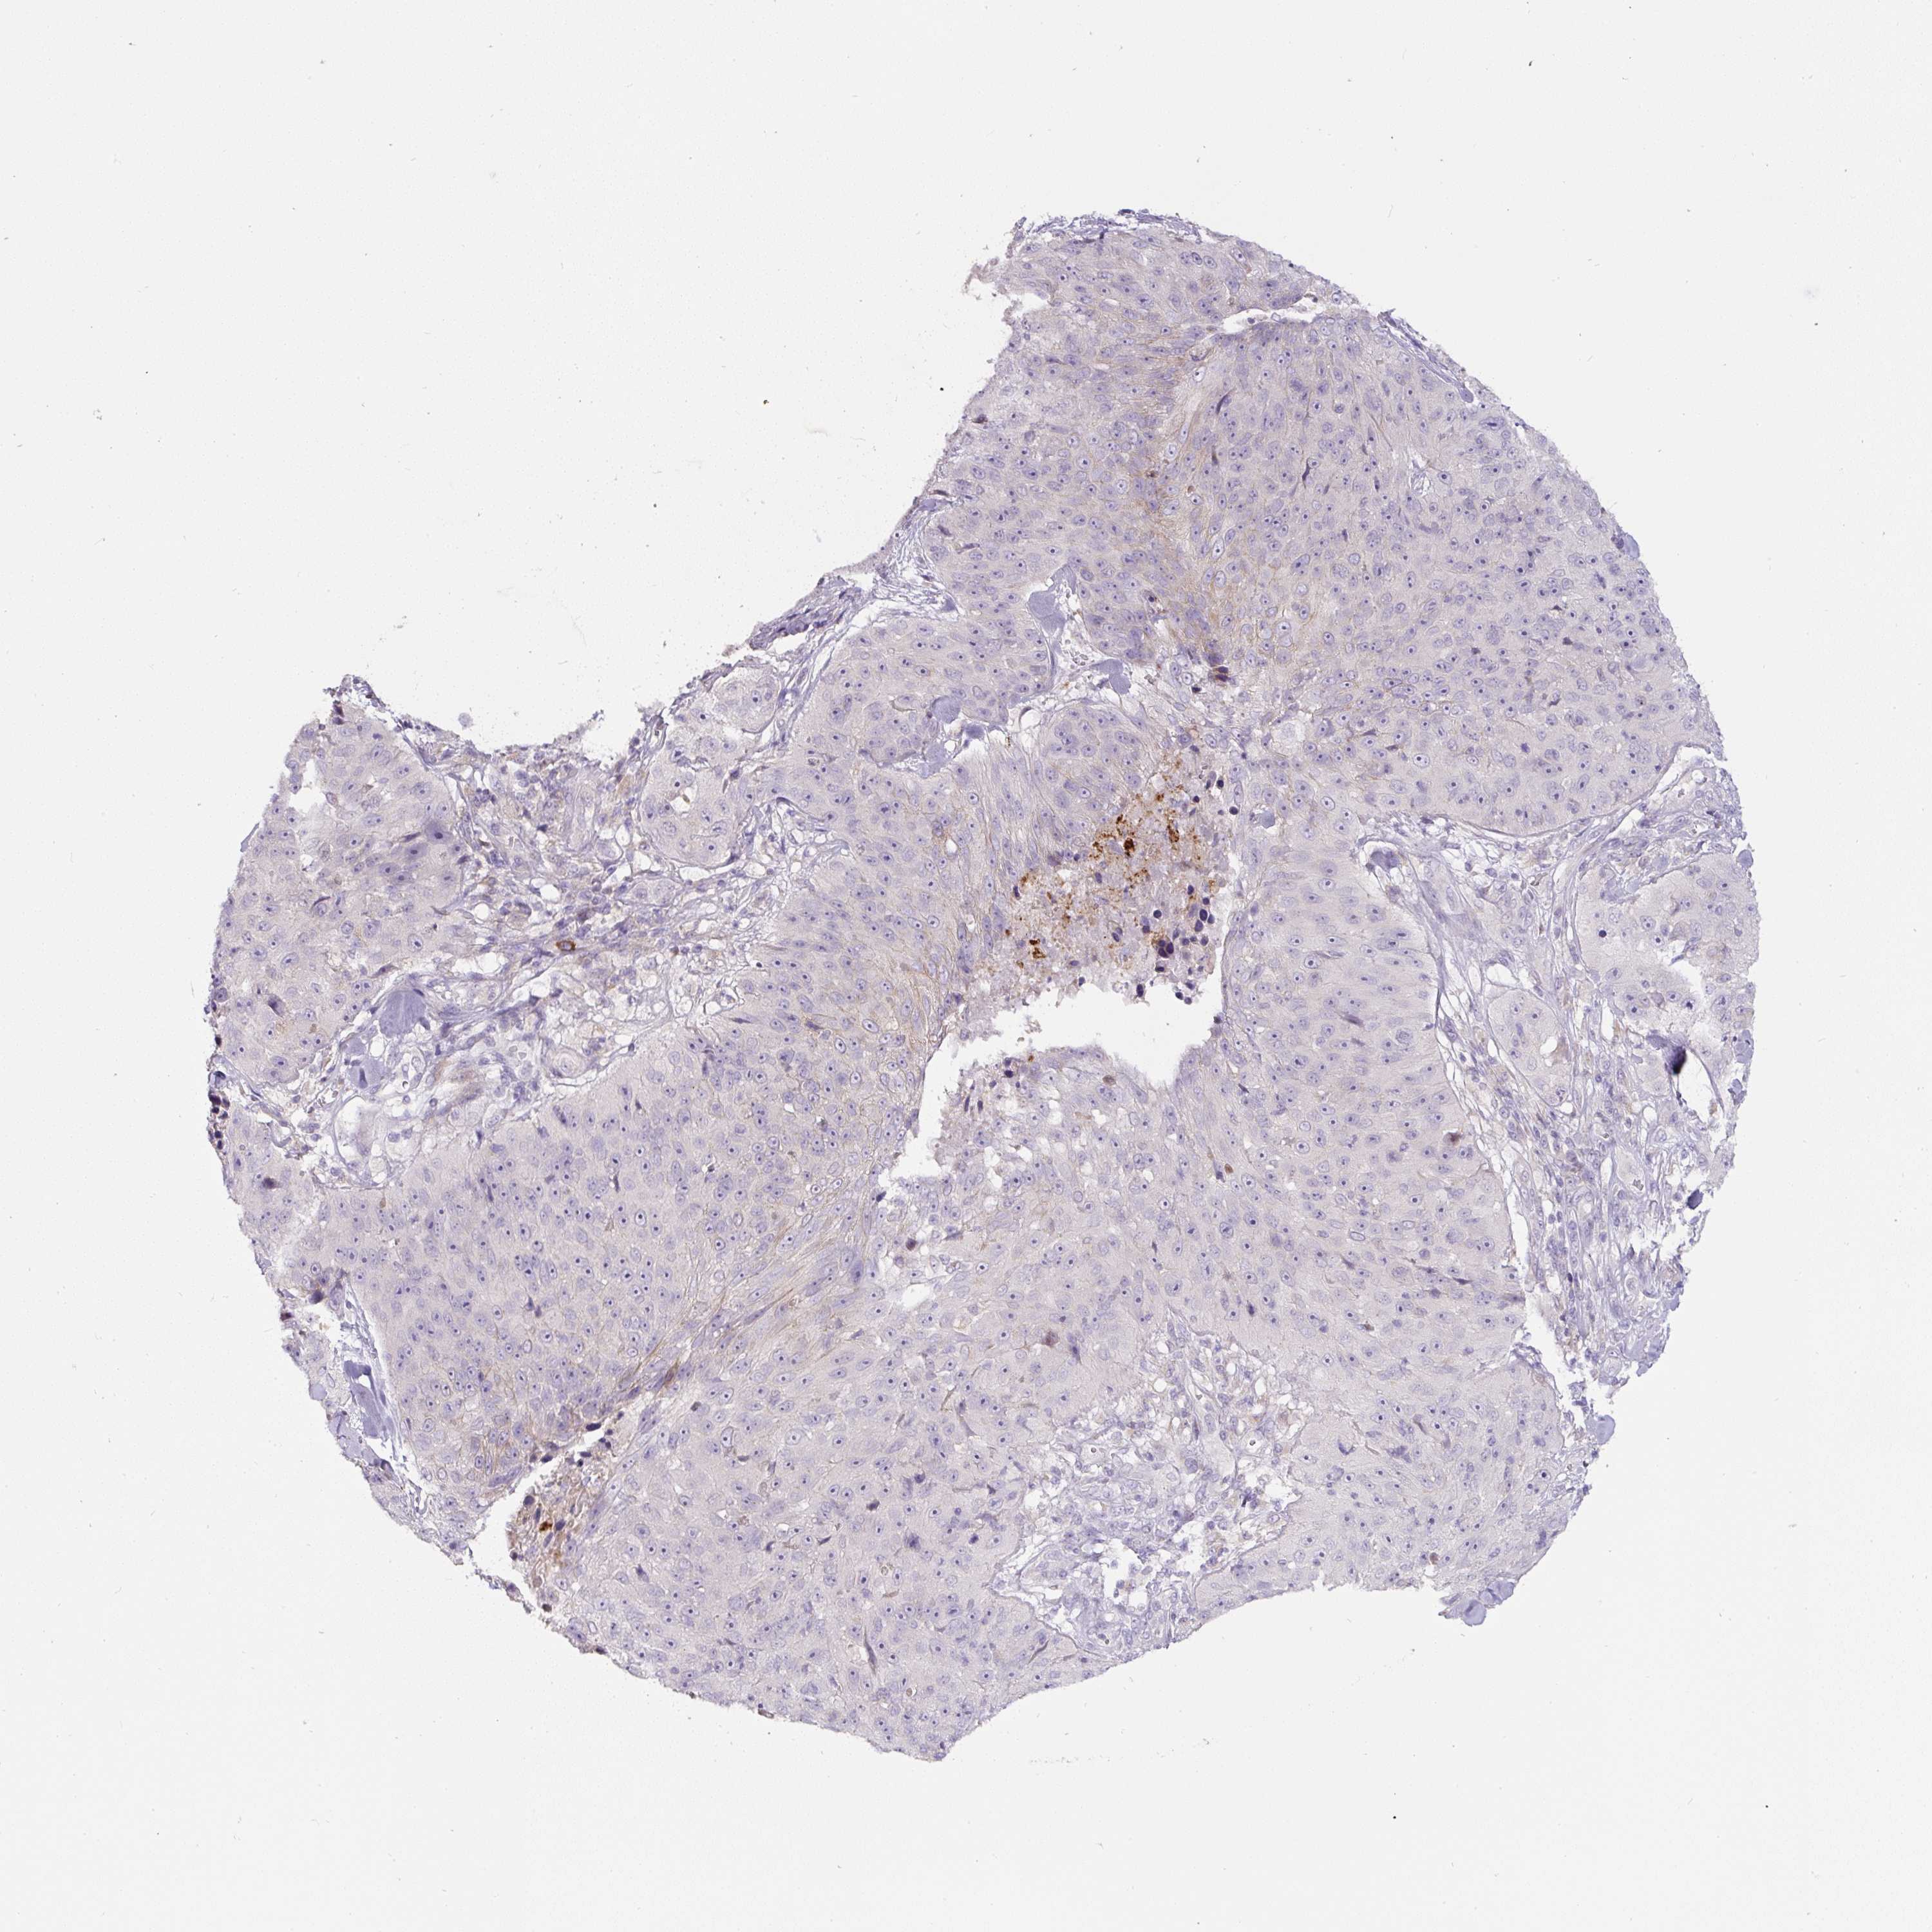

CANCER SKIN CANCER Show tissue menu

Basal cell and squamous cell cancer

SKIN CANCER - Protein expressioni

A mouse-over function shows sample information and annotation data. Click on an image to view it in a full screen mode. Samples can be filtered based on level of antibody staining by selecting one or several of the following categories: high, medium, low and not detected. The assay and annotation is described here.

Each image is clickable and will lead to virtual microscopy that enables deeper exploration of all samples and also displays staining intensity scores, fraction scores and subcellular localization as well as patient and tissue information for each sample.

Antibody HPA050189

Antibody CAB033106

Basal cell carcinoma

Squamous cell carcinoma, NOS

Squamous cell carcinoma, metastatic, NOS